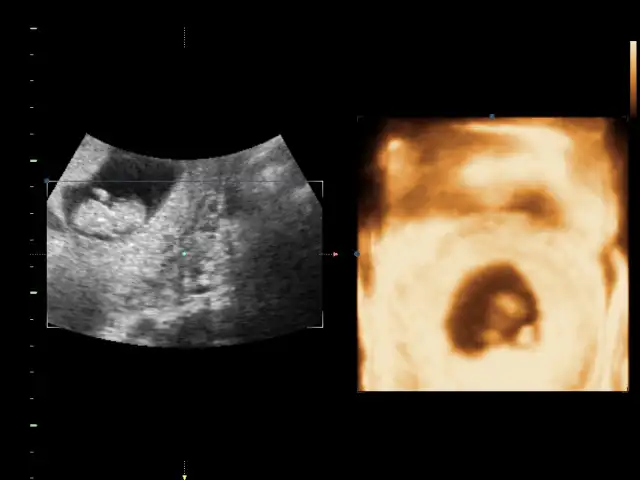

Bu bebek durusu degisik geldi goremedim bisey canim

Bacakları açık aslında hiç çıkıntı yok gibiBu bebek durusu degisik geldi goremedim bisey canim

Kıza benziyor bence.Fikri olan var mı acabaEki Görüntüle 1530236

Kiz bence cikinti yokFikri olan var mı acabaEki Görüntüle 1530236

Canım kıza daha çok benzettim ben :)